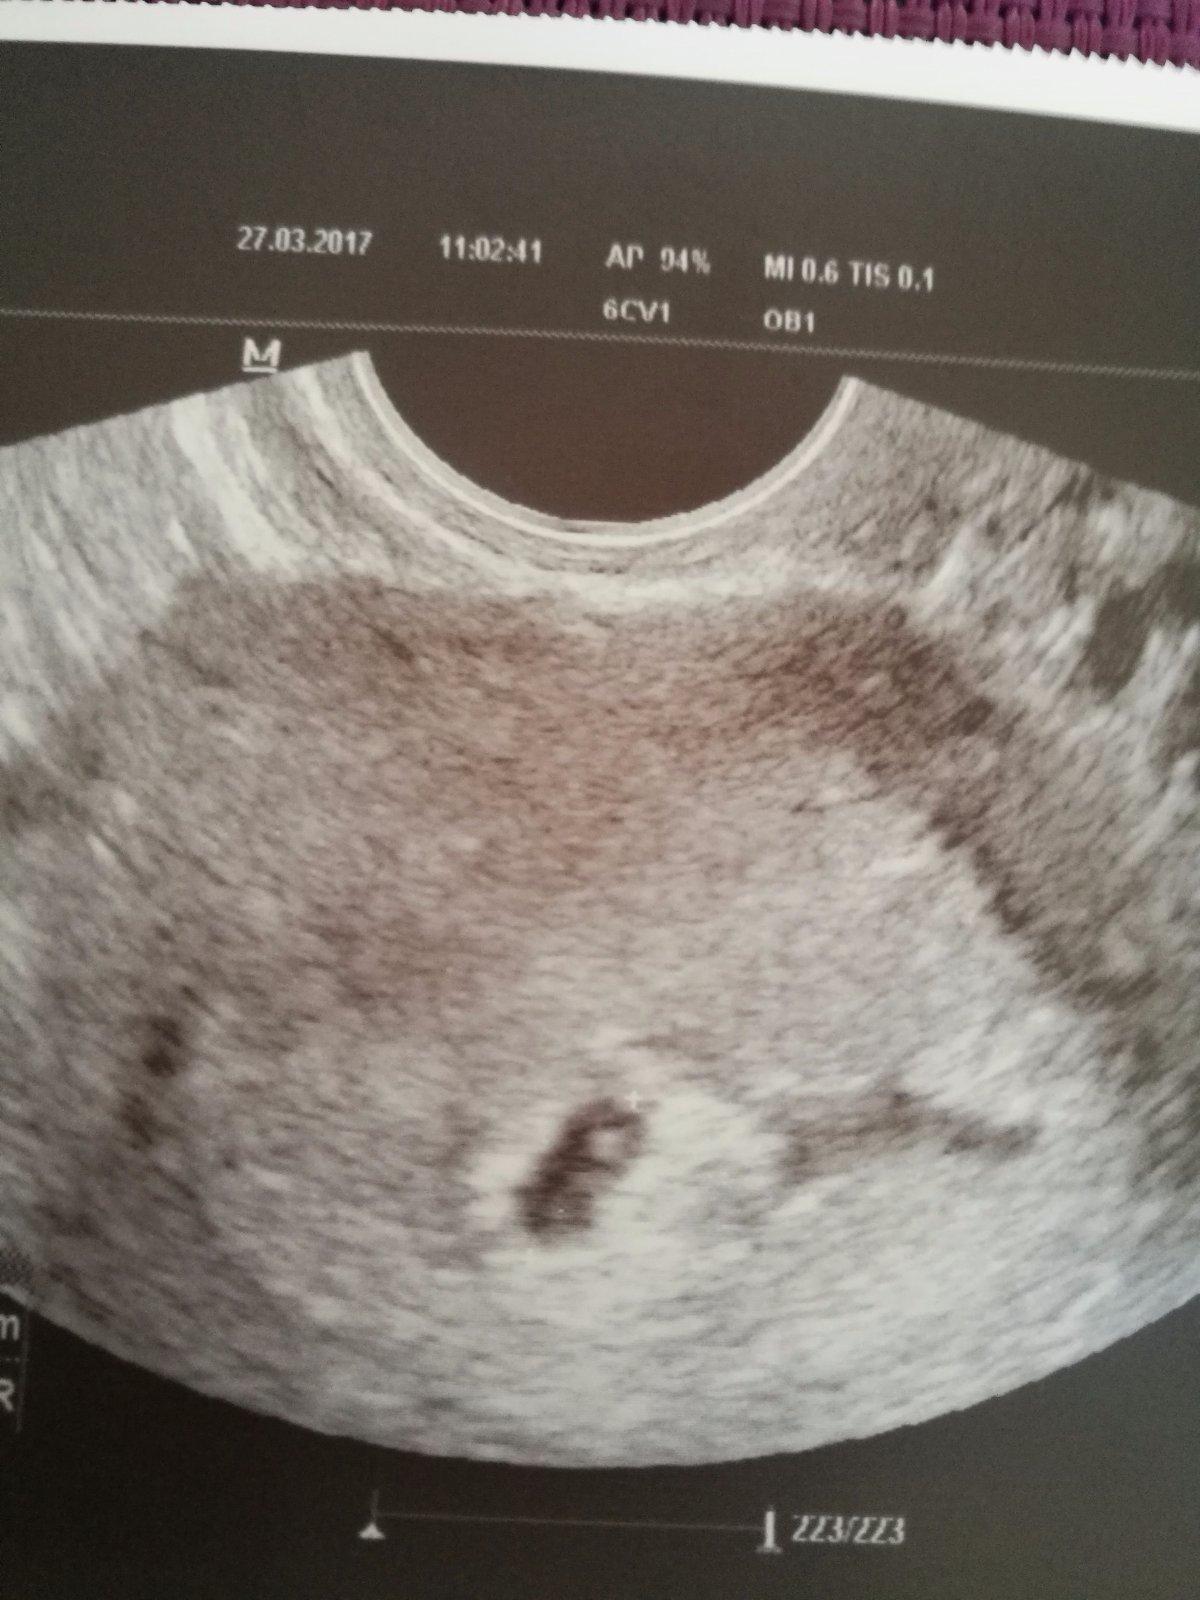

Dnešní dle utz 5+3 dle ms 6+0 💕

autor@kloky1 kdy byla poslední ms? Koukala jsem na vas test a ještě není úplně silný rekla bych že jsi tak ve tretim týdnu těhotenství ... můj gestracni vacek má 7mm a prcek tak dva mm roste ted hodně rychle za tech 10 dní bude mít vacek tak 1,5mm a plod tak 4-5 ...těhotenství je zcela nečekané ale jsem moc šťastná ted jen čekáme na srdíčko a budu ještě šťastnější 💕 bolí tě brisko a prsa?

Krasne, gratuluji! Bylo videt i srdicko?